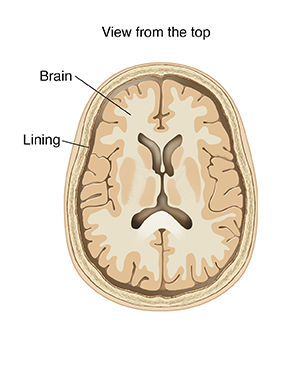

Meningitis

Meningitis is inflammation of the lining around the brain and spinal cord (meninges). It’s most often caused by germs that infect the fluid and lining. Types of meningitis include: